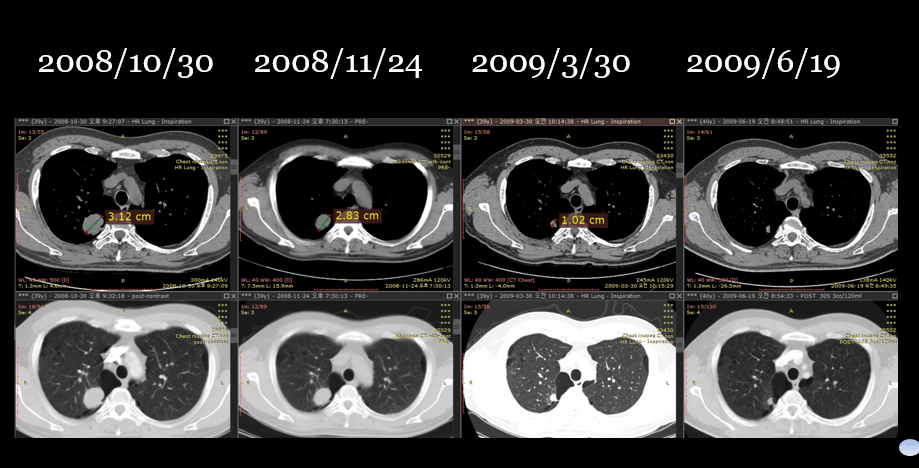

Imaging studies revealed:

A primary lung mass

A large abdominal mass

Adrenal gland metastasis

This constellation of findings indicated advanced-stage disease,

consistent with sarcomatoid carcinomatosis with systemic dissemination.

At initial evaluation, the abdominal tumor measured

5.8 × 5.7 × 6.0 cm, corresponding to approximately 102.8 cm³ in volume.

Both adrenal and pulmonary lesions measured approximately 3–4 cm.

The initial prognosis, as estimated at a tertiary center,

was approximately 3 months of expected survival.

However, following therapeutic intervention,

the tumor demonstrated an extraordinary response.

Within just 28 days,

tumor volume decreased from 102.8 cm³ to 16 cm³,

representing an 84% reduction.

By day 40,

the tumor further decreased to 6 cm³,

corresponding to a 94% reduction from baseline.

The tumor continued to regress over time:

Within 3 months, near-complete regression was observed

At 5 months, the abdominal mass became radiologically undetectable

Adrenal metastasis disappeared completely

Lung lesions showed only minimal residual disease

Subsequently, small residual lesions fluctuated in size,

ranging between 0.6 and 1.7 cm³,

suggesting minimal residual disease rather than active progression.